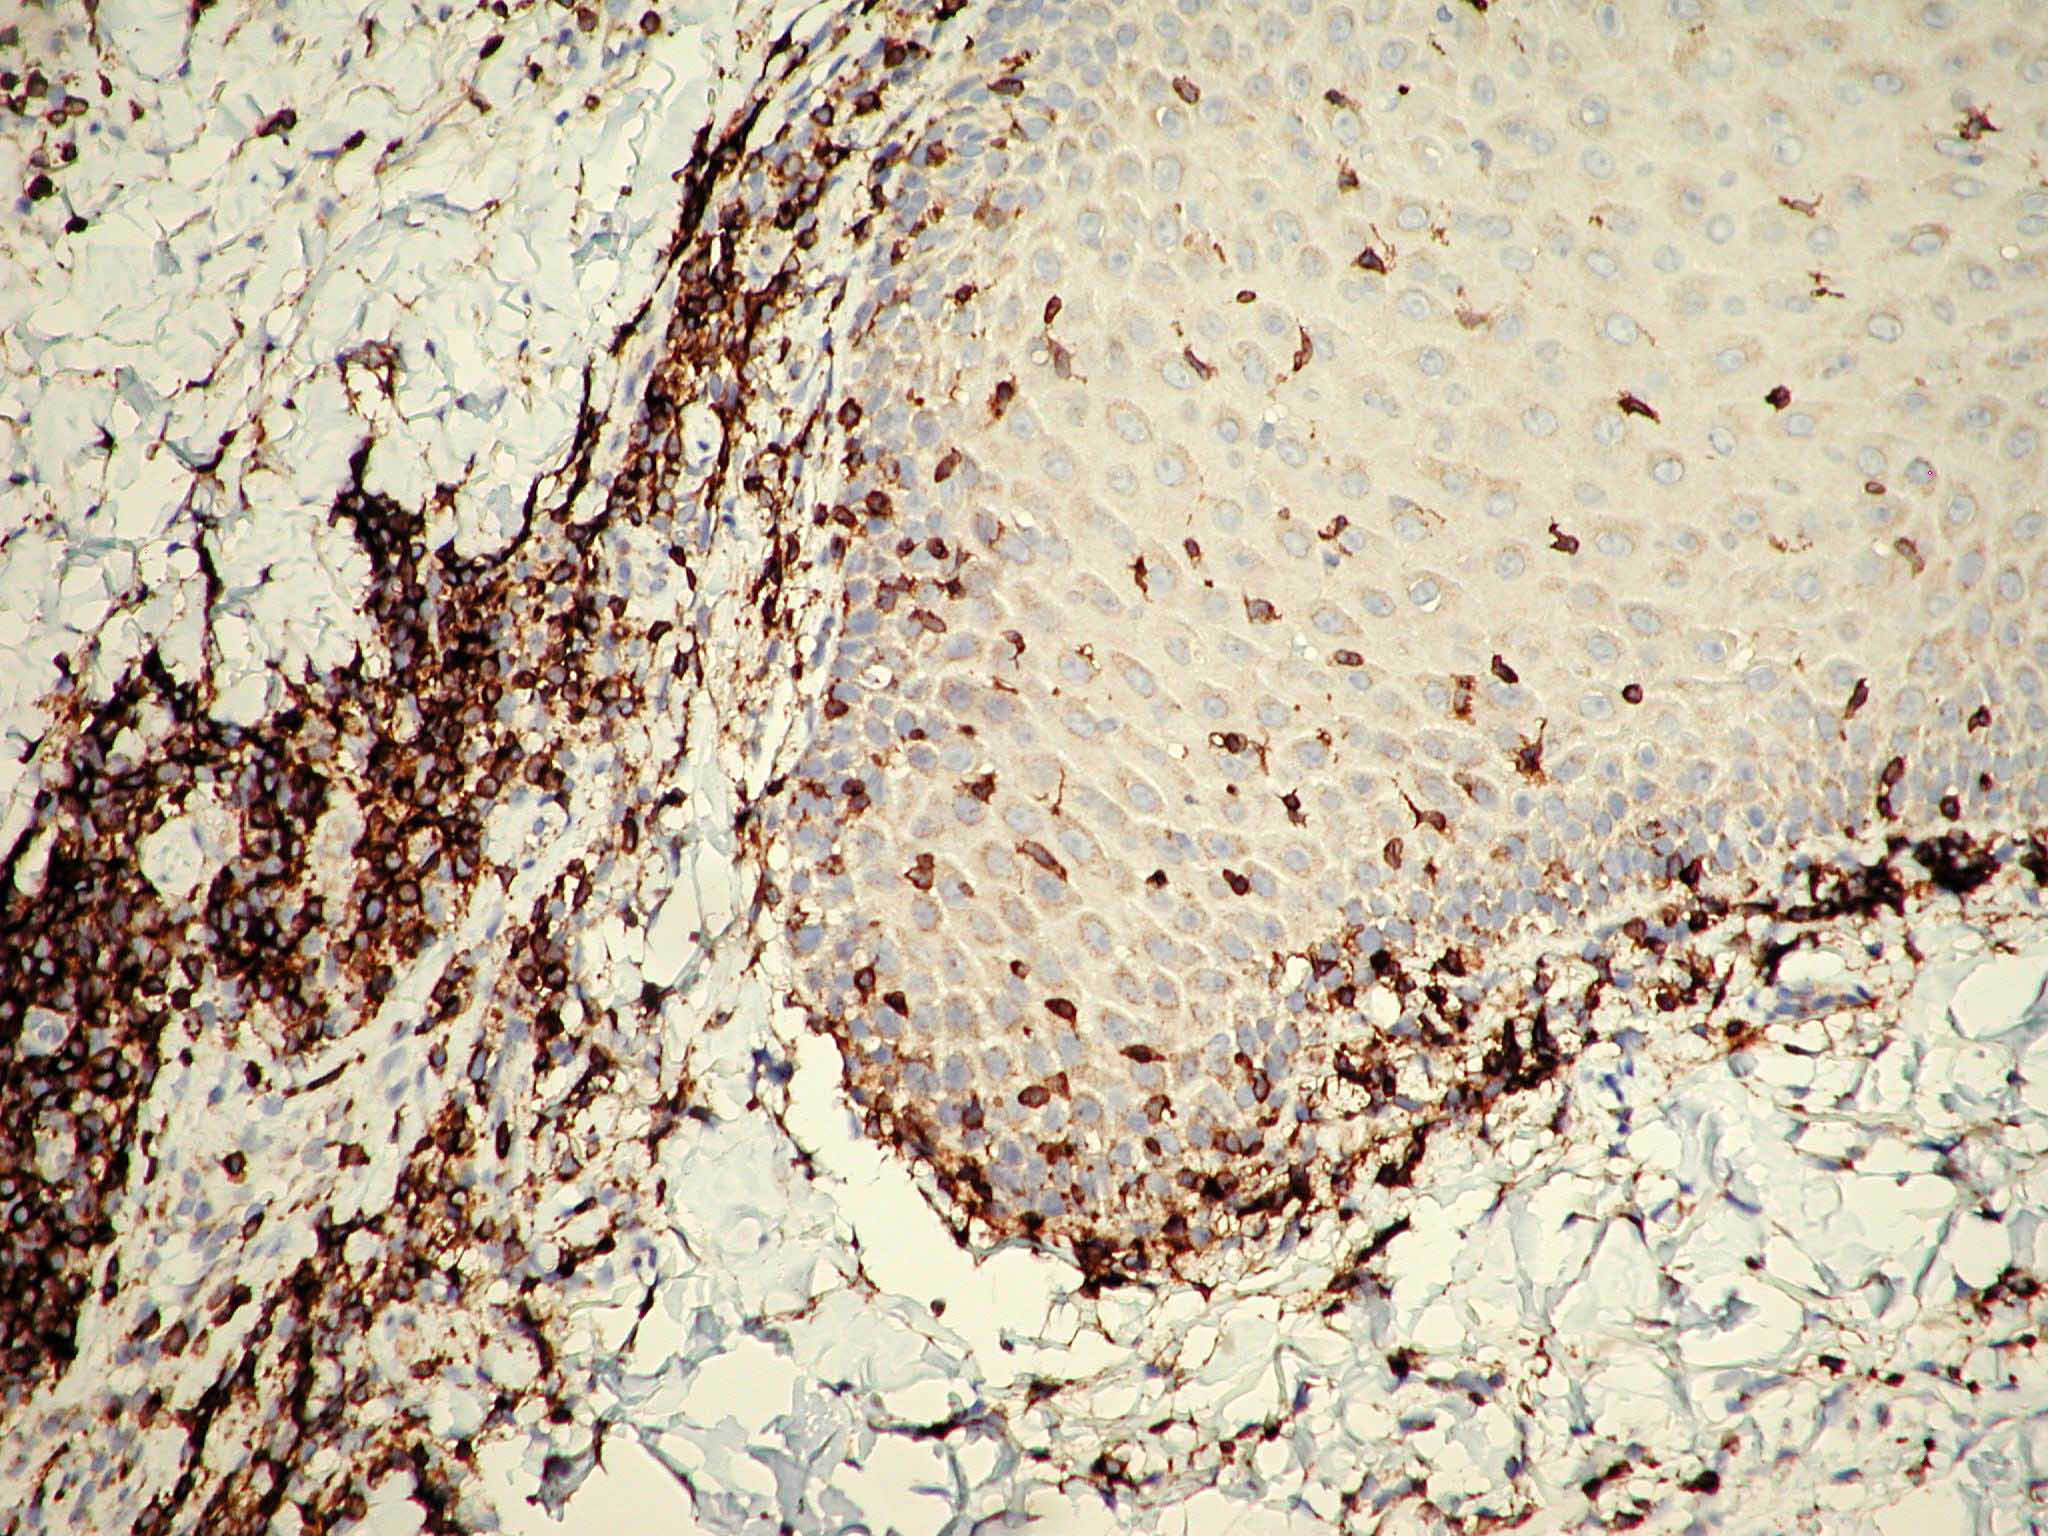

Mycosis Fongoïde =التفطر الكمئي